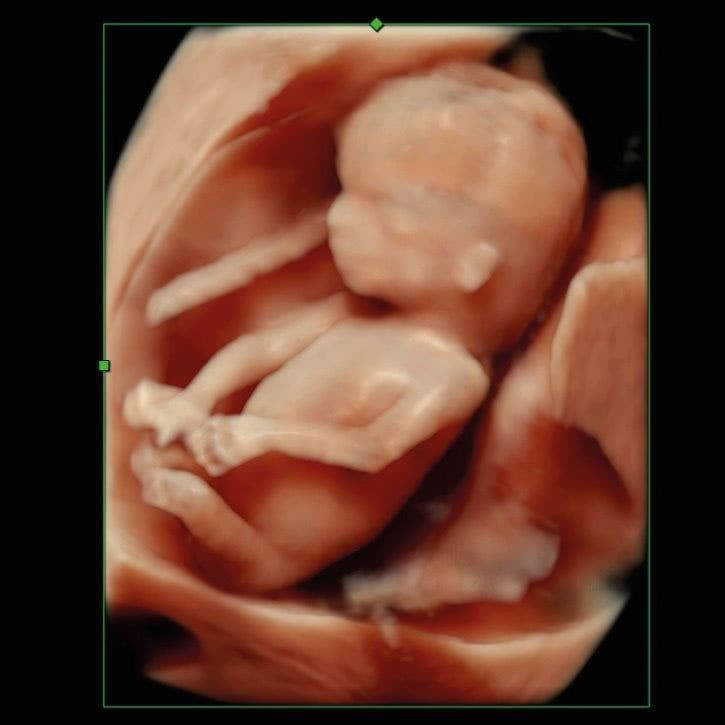

Im ersten Trimenon (1. Schwangerschaftsdrittel) bieten wir Ihnen verschiedene Untersuchungen an. Ab der 12. SSW können unter anderem bereits Kopf, Herz und Extremitäten untersucht und einige Fehlbildungen ausgeschlossen werden.

Im Ersttrimesterscreening (12-14 SSW) können wir durch Messen der Nackentransparenz, Darstellung des Nasenbeins und weitere Parameter zusätzlich das Risiko für Chromosomenstörungen bei Ihrem Kind ermitteln.